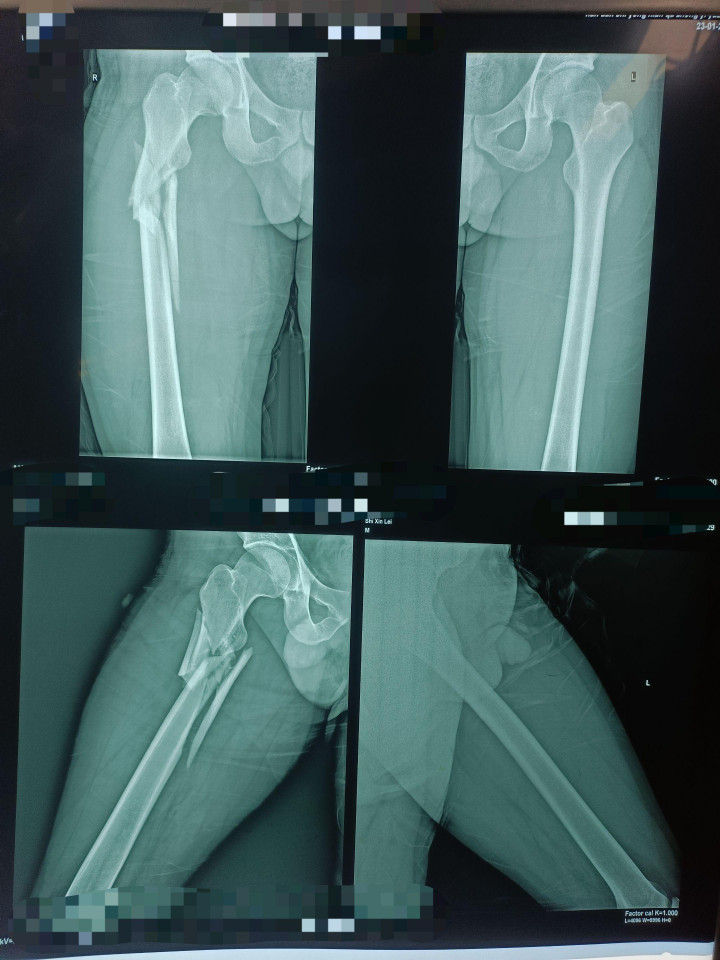

中股网 外伤导致的股骨上段骨折闭合复位股骨重建钉固定,期待早期愈合